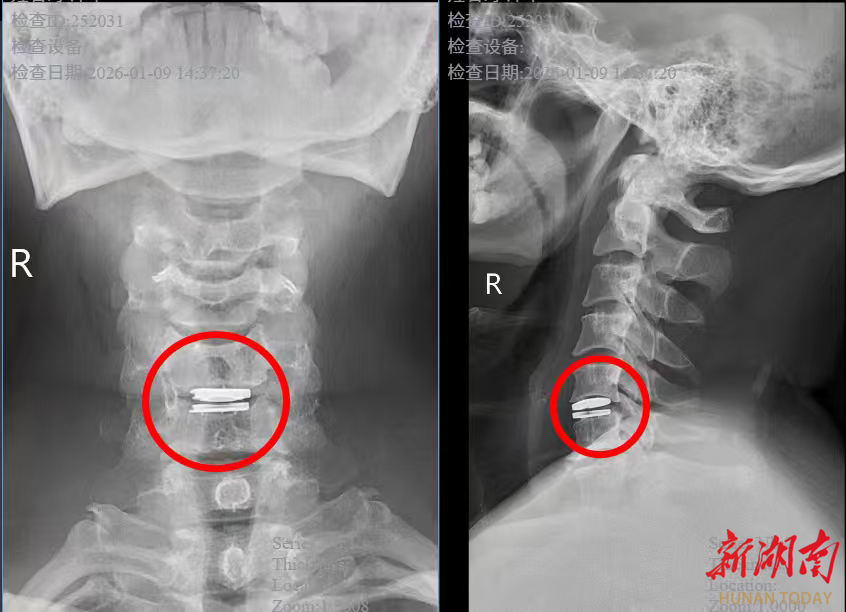

手术当天,脊柱外科唐光副主任医师在高清显微镜的精准引导下,通过一个微创小切口,精准摘除病变椎间盘,植入适配的人工椎间盘假体,完美恢复颈椎正常生理曲度和椎间高度。整个手术出血量极少,神经保护精准到位,真正实现了“微创、精准、安全”的治疗目标。

术后恢复速度远超李先生预期:术后第1天,颈肩疼痛和双上肢麻木症状就明显缓解,能够自主翻身、坐起;术后第2天,在医生指导下顺利下床行走,颈部活动灵活无受限,经影像学检查确认人工椎间盘位置精准、稳定性良好;术后第5天,李先生各项指标均达到出院标准,带着满意的笑容顺利出院。“原以为颈椎手术要躺很久,没想到这么快就能正常活动,医生技术太厉害了!”出院时,李先生带着家属,向脊柱外科团队表达了由衷的感谢。